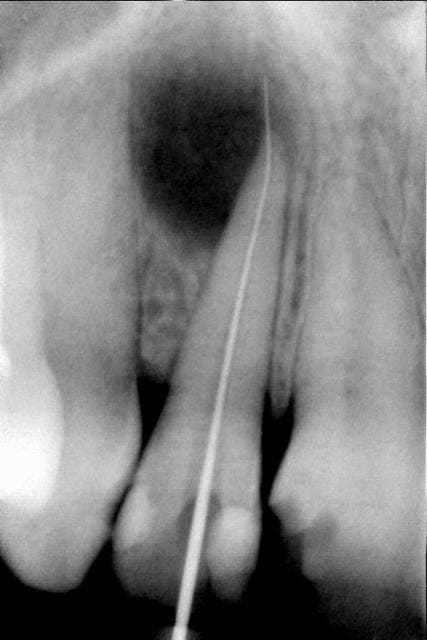

voici un cas.

j'en ai à la pelle des comme ça, même qui concernent plusieurs dents.

le traitement le plus simple possible: endo+ curetage+ fermeture.